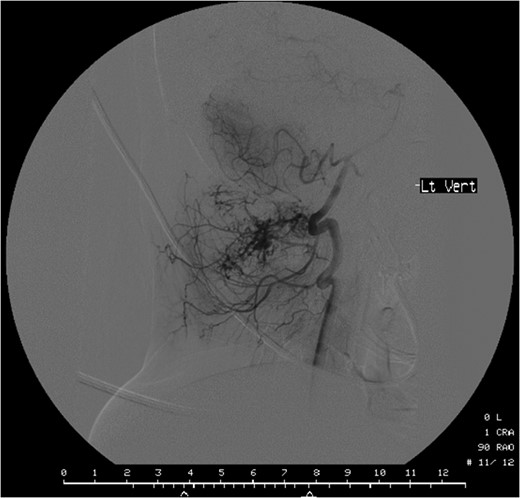

Computed tomographic angiography of the left vertebral artery showing the tumour deriving its vascular supply from the cervical and muscular branches of the artery.